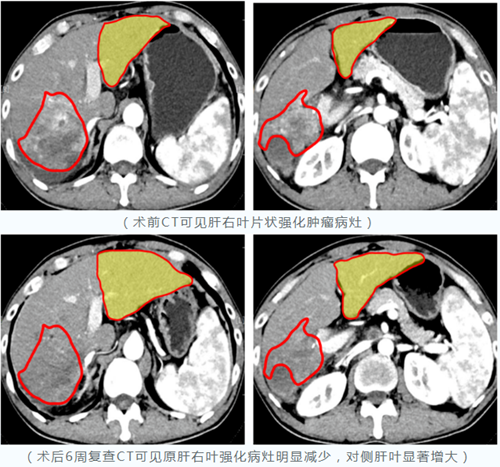

自2023年3月10日釔-90微球治療肝腫瘤項目落地西安國際醫(yī)學(xué)中心醫(yī)院以來,已有數(shù)十例肝癌患者經(jīng)篩選、評估并成功接受治療。術(shù)后復(fù)查結(jié)果顯示:釔-90“殺瘤”效果顯著,大肝癌或巨塊型肝癌經(jīng)治療后病灶明顯縮小,部分患者殘肝體積明顯增大;……